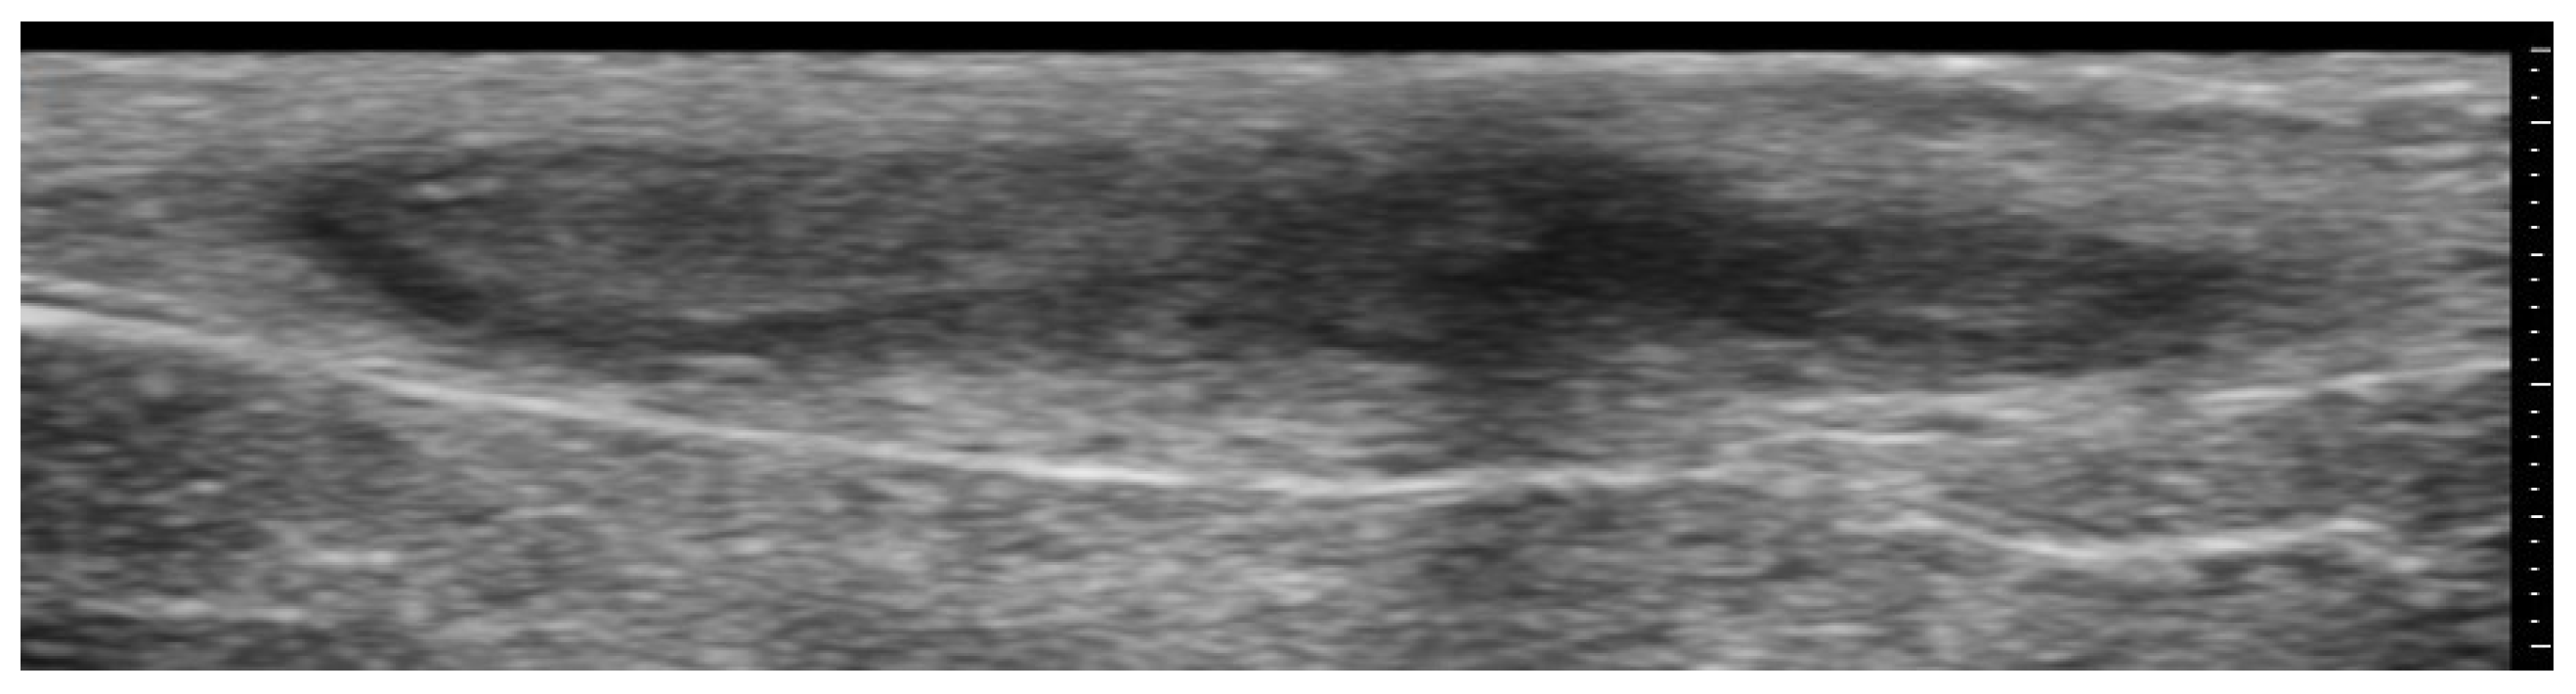

2. Infections